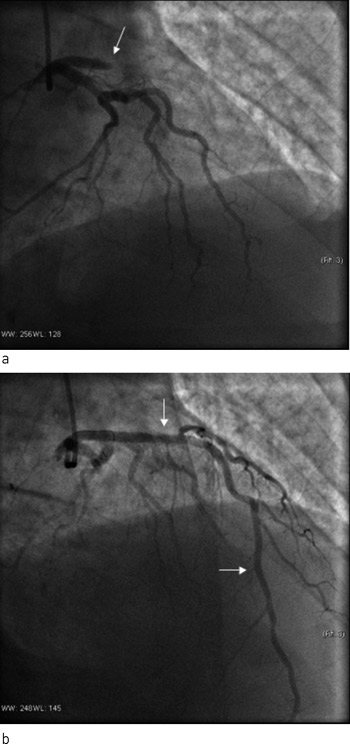

Nytt EKG viste nytilkomne ST-hevninger i fremreveggsavledningene som ga mistanke om reokklusjon av behandlet koronararterie. Ny koronarangiografi viste okkluderende trombe ved inngangen til stenten og i hele det tidligere stentede området (fig 1). Man valgte å gi ufraksjonert heparin og abciximab (en glykoprotein IIb/IIIa-hemmer) samt utføre ny PCI med stenting av proksimale venstre fremre koronararterie. Det angiografiske resultatet var godt, pasienten ble raskt smertefri og det tilkom ingen ny økning i CK eller troponin T.